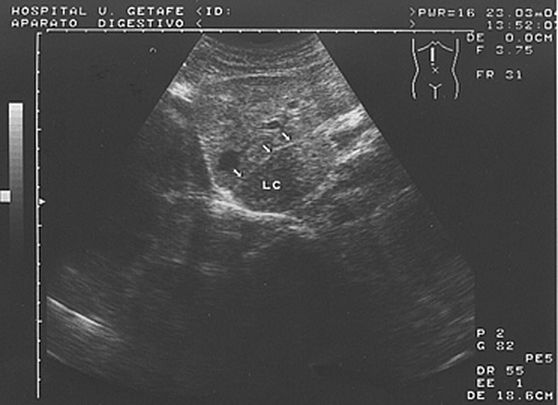

1.1. Anatomía normal

Dr. Mariano Gómez Rubio (Getafe)